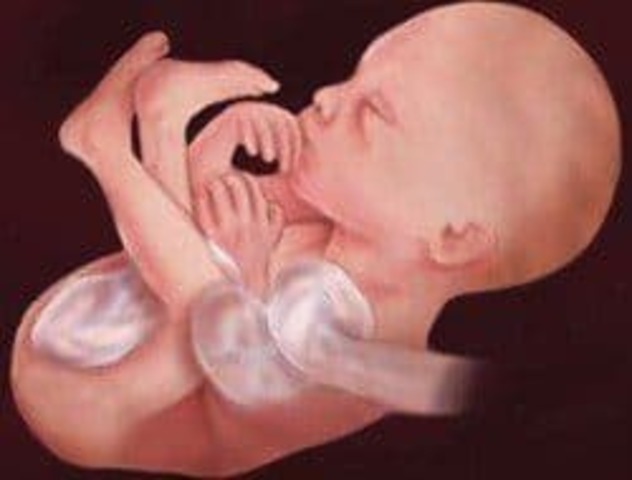

Todos los sistemas principales del cuerpo y órganos como el estómago, el hígado, los pulmones, el páncreas y los intestinos están formados y en su sitio, aunque no están desarrollados del todo. La cabeza llega a ser más redondeada y su perfil se va definiendo.

Todavía mide 6 centímetros y tiene unos 14 gramos de peso.

Durante esta semana de embarazo las orejas y los ojos se están moviendo hacia su posición. Ya han aparecido los 27 huesos de la mano y pronto el bebé comenzará a chuparse el dedo.

• Semana Catorce

Semana Catorce

Ya tendrá las orejas en su lugar definitivo aunque seguirán creciendo a lo largo de las semanas siguientes.

Puede que haga sus primeros movimientos con la cabeza. Podrá moverla de un lado a otro. No será hasta la semana siguiente cuando aparezcan los primeros movimientos similares a los de una actividad respiratoria: dilataciones y contracciones de la caja torácica.

Ya tendrá entre 80 y 93 mm y su peso será de unos 30 gramos